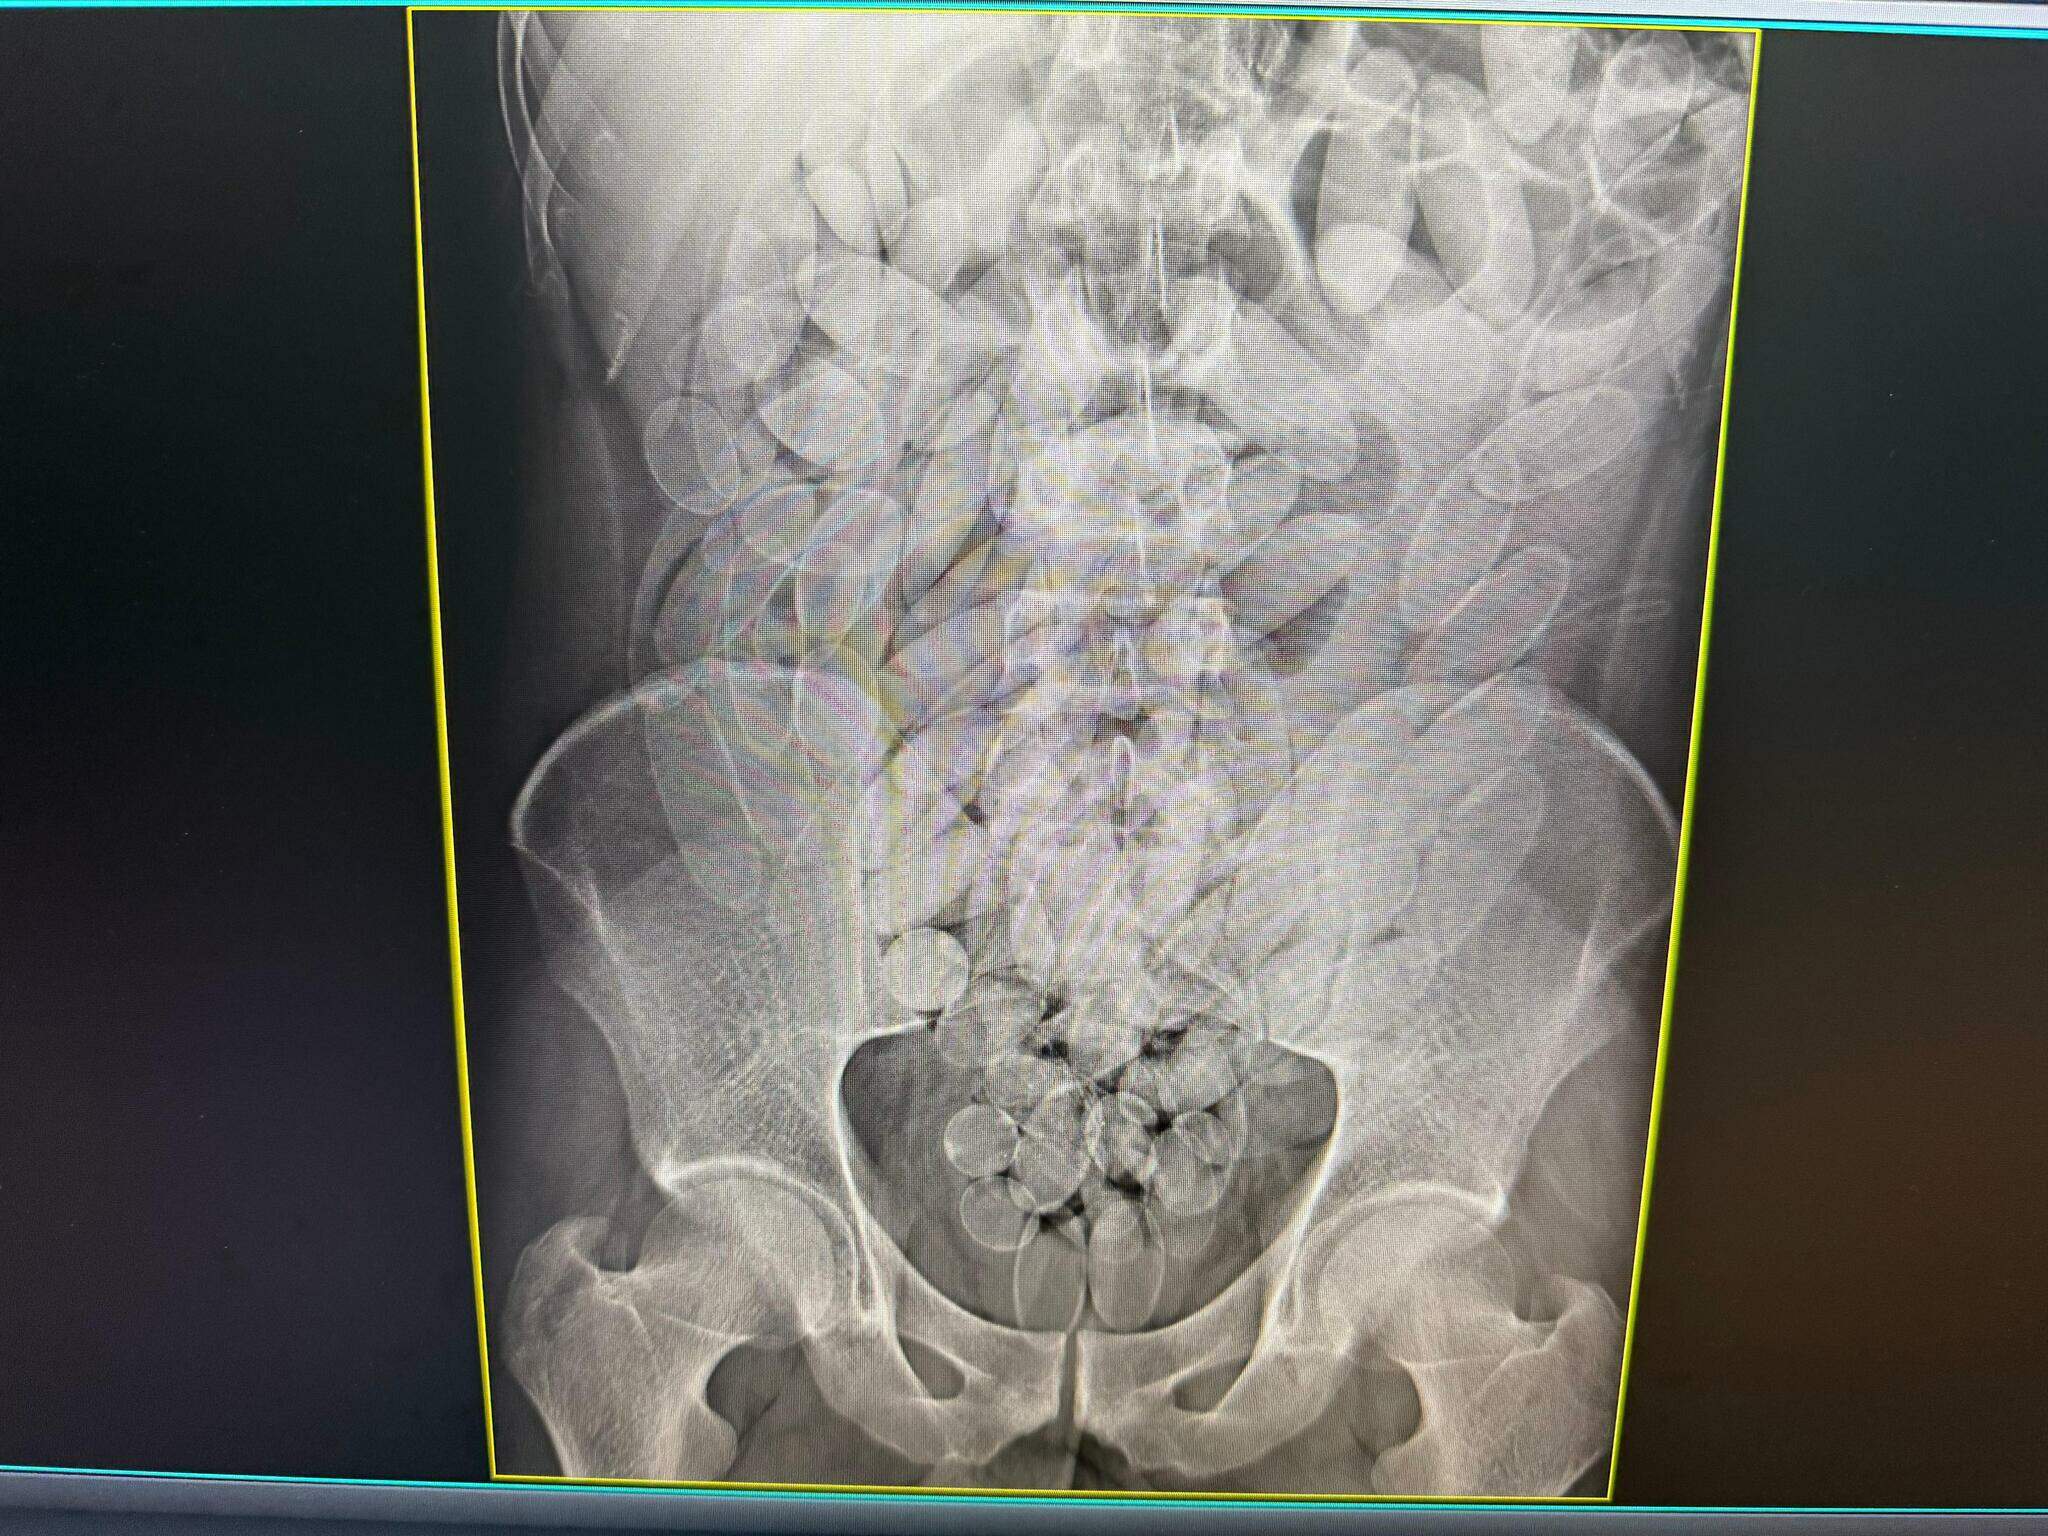

Os raios X confirmaram que os oito haviam engolido cápsulas com substância análoga à pasta base de cocaína. O material foi retirado de forma segura por equipe médica, totalizando 645 cápsulas. Após o procedimento, todos foram encaminhados à Polícia Federal, onde permanecem à disposição da Justiça.